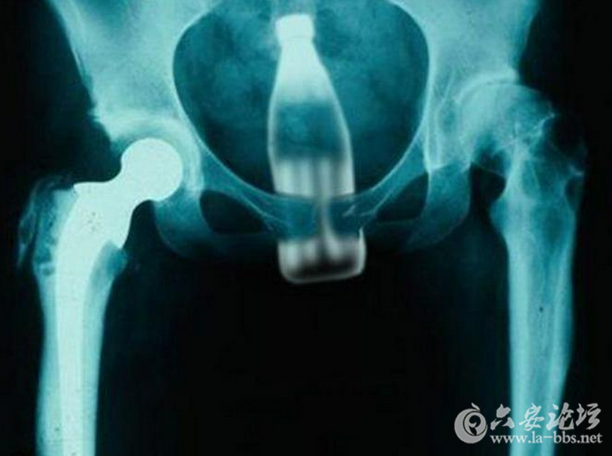

这些让人瞠目结舌的X光片,映射出了女人下体的那点儿事儿,对性有需求是好的,可是要是乱放东西,伤到身体,那可麻烦大了!

可乐瓶塞进下体这件事儿,相信大家都有所耳闻,毕竟瓶口的光滑度和粗细都是人体可以接受的,但是如果将平身都塞进去,可是有点儿狠。